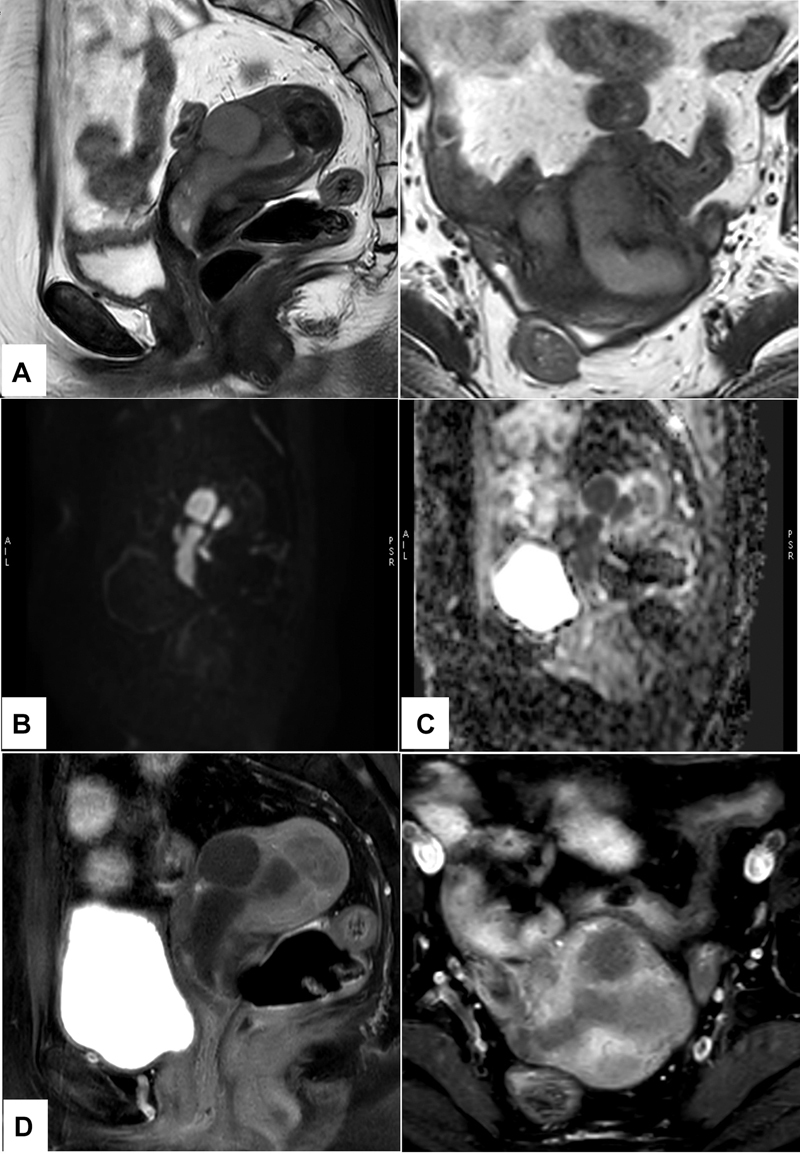

急性淋巴细胞白血病/淋巴瘤(ALL)髓外浸润到生殖器官是非常罕见的。在这里,我们报告一例无症状的49岁女性,已知的前体b细胞ALL病例,偶然发现超声增厚和异质高回声子宫内膜。磁共振造影示大息肉样增强病灶,弥散受限,占据子宫内膜腔,左侧附件、左侧卵巢、输卵管均见类似病灶,临床病史及外观不典型,怀疑白血病浸润。18 f -氟脱氧葡萄糖正电子发射断层扫描/计算机断层扫描(18 F-FDG PET/CT)显示子宫内膜腔、左附件、大网膜结节、腹膜后淋巴结、胰腺病变强烈代谢活跃,右下叶少量不规则结节。活检结果证实ALL髓外复发。因此,18f - fdg PET/CT可以作为一个很好的全身检查来寻找髓外复发部位。

Extramedullary infiltration of acute lymphoblastic leukemia/lymphoma (ALL) to genital organs is extremely rare. Here, we present a case report of an asymptomatic 49-year-old female, known case of precursor B-cell ALL, who was incidentally detected with thickened and heterogeneously hyperechoic endometrium on sonography. Contrast magnetic resonance imaging detected large polypoidal enhancing lesions showing intense diffusion restriction occupying the endometrial cavity and similar lesions in the left adnexa, left ovary, and fallopian tube which were suspicious for leukemic infiltration because of the clinical history and atypical appearance of the lesions. 18 F-fluorodeoxyglucose positron emission tomography/computed tomography ( 18 F-FDG PET/CT) was done which revealed intensely metabolically active lesion in the endometrial cavity, left adnexa, omental nodules, retroperitoneal lymph node, pancreatic lesion, and few irregular nodules in the right lower lobe. Biopsy findings confirmed extramedullary relapse of ALL. Hence, 18 F-FDG PET/CT can act as a good whole body survey to look for extramedullary sites of relapse.